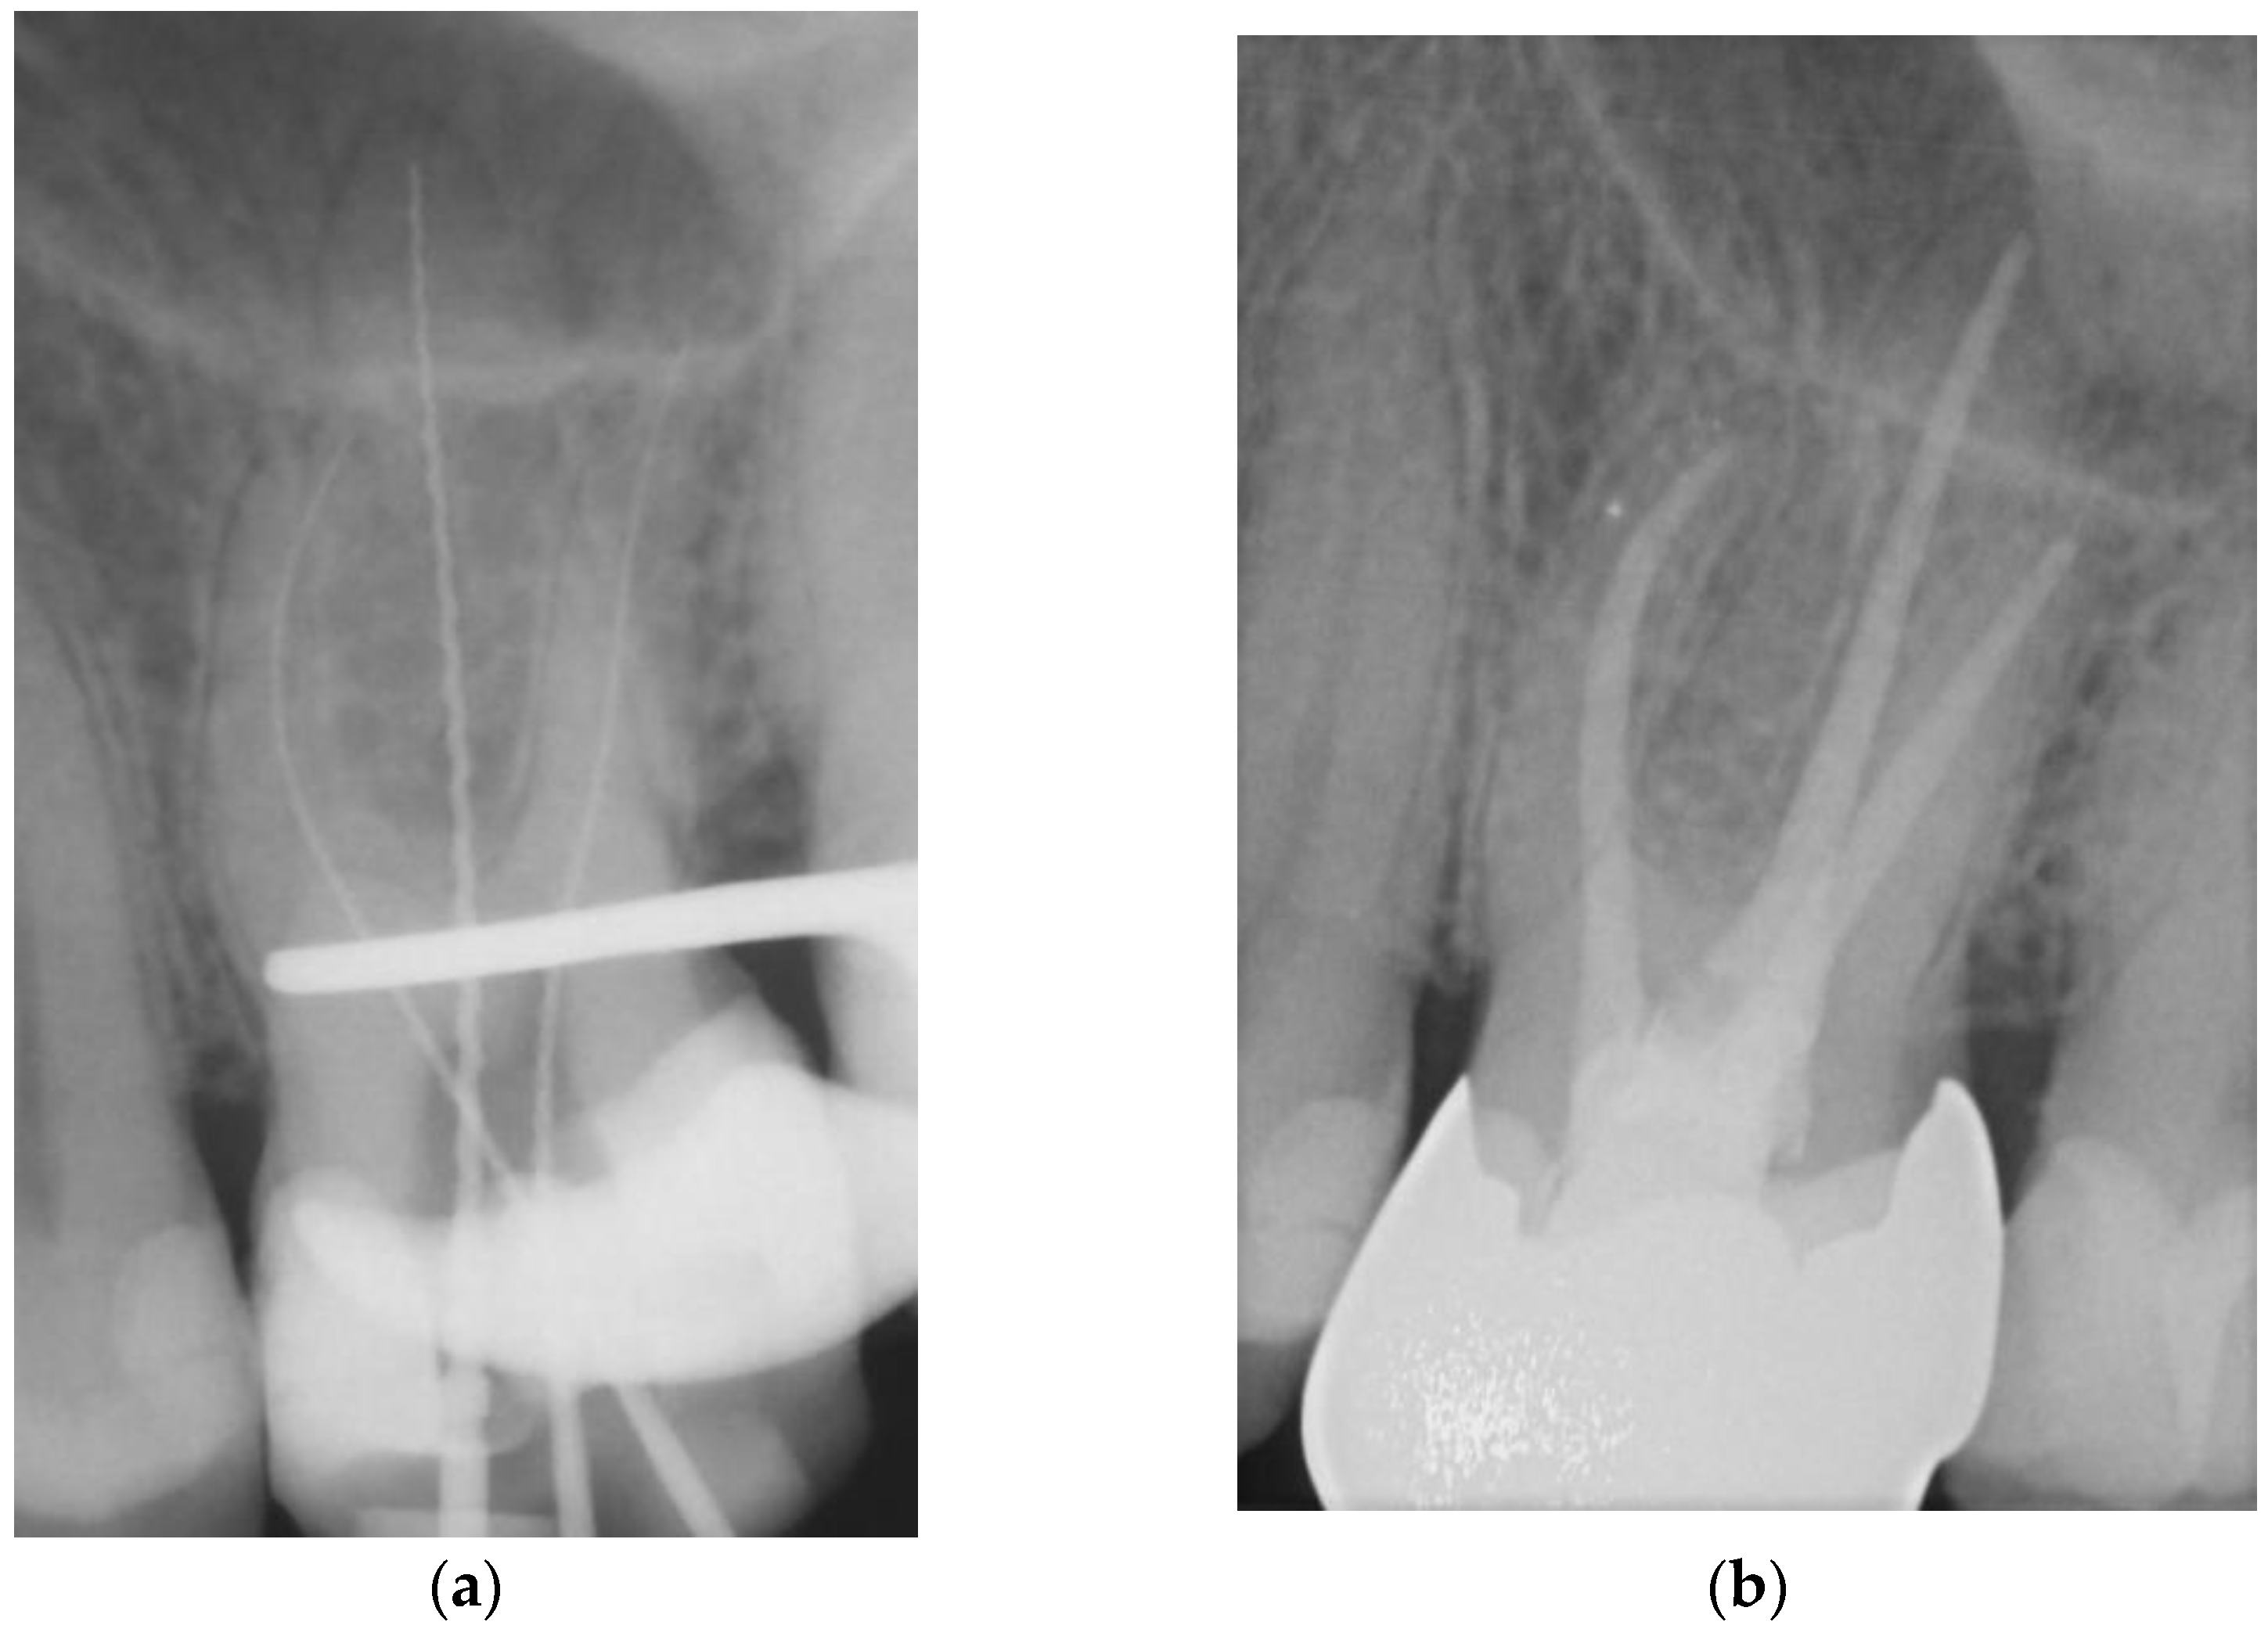

Figure 2. Representative example of root canal filling using the single-cone obturation technique with gutta-percha and AH Plus® (SCGP); working length radiograph of tooth 26 (a); 7-year follow-up radiograph showing complete apical healing (b). - Matching-taper single-cone obturation with gutta-percha and the silicon-based sealer GuttaFlow® (SCGF) (Figure 3).

Figure 3. Representative root canal filling using the single-cone obturation technique with gutta-percha and GuttaFlow® (SCGF); working length radiograph of tooth 46 (a); 6-year follow-up radiograph showing complete apical healing (b).